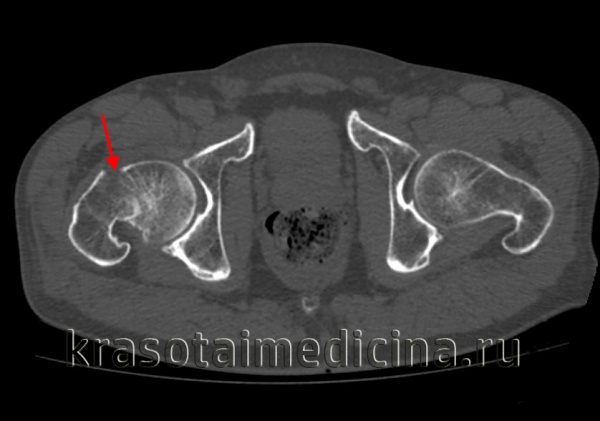

Признаки перелома головки бедренной кости

Перелом головки бедренной кости. Диагностика и лечение

Для выявления переломов этого типа достаточно, как правило, обычных рентгенограмм в прямой проекции и в проекции с наружной и внутренней ротацией бедра. Диагностике скрытых переломов часто помогают рентгенограммы в сравнительных проекциях. У всех больных с подозрением на перелом бедра должна быть тщательно изучена линия Шентона. Кроме того, при подозрении на перелом необходима оценка шеечно-диафизарного угла, который в норме составляет 120—130°. Его измеряют от точки линий пересечения, проведенных по осям диафиза и шейки бедренной кости.

Класс А: перелом головки бедренной кости

Перелом головки бедренной кости встречается редко и может проявиться в сочетании с вывихом или без какой-либо значительной деформации. Его классифицируют по двум типам на основании размера и количества фрагментов. При переломах I типа имеется один фрагмент, в то время как переломы II типа являются оскольчатыми.

Для выявления этих переломов достаточно снимков тазобедренного сустава в обычных проекциях.

Оскольчатые переломы могут сочетаться с переломами таза или верхней конечности на стороне повреждения. Задние переломовывихи сопровождаются повреждениями седалищного нерва, переломами костей таза нижней конечности на стороне повреждения. Передним переломовывихам могут сопутствовать повреждения артерий или тромбоз вен.